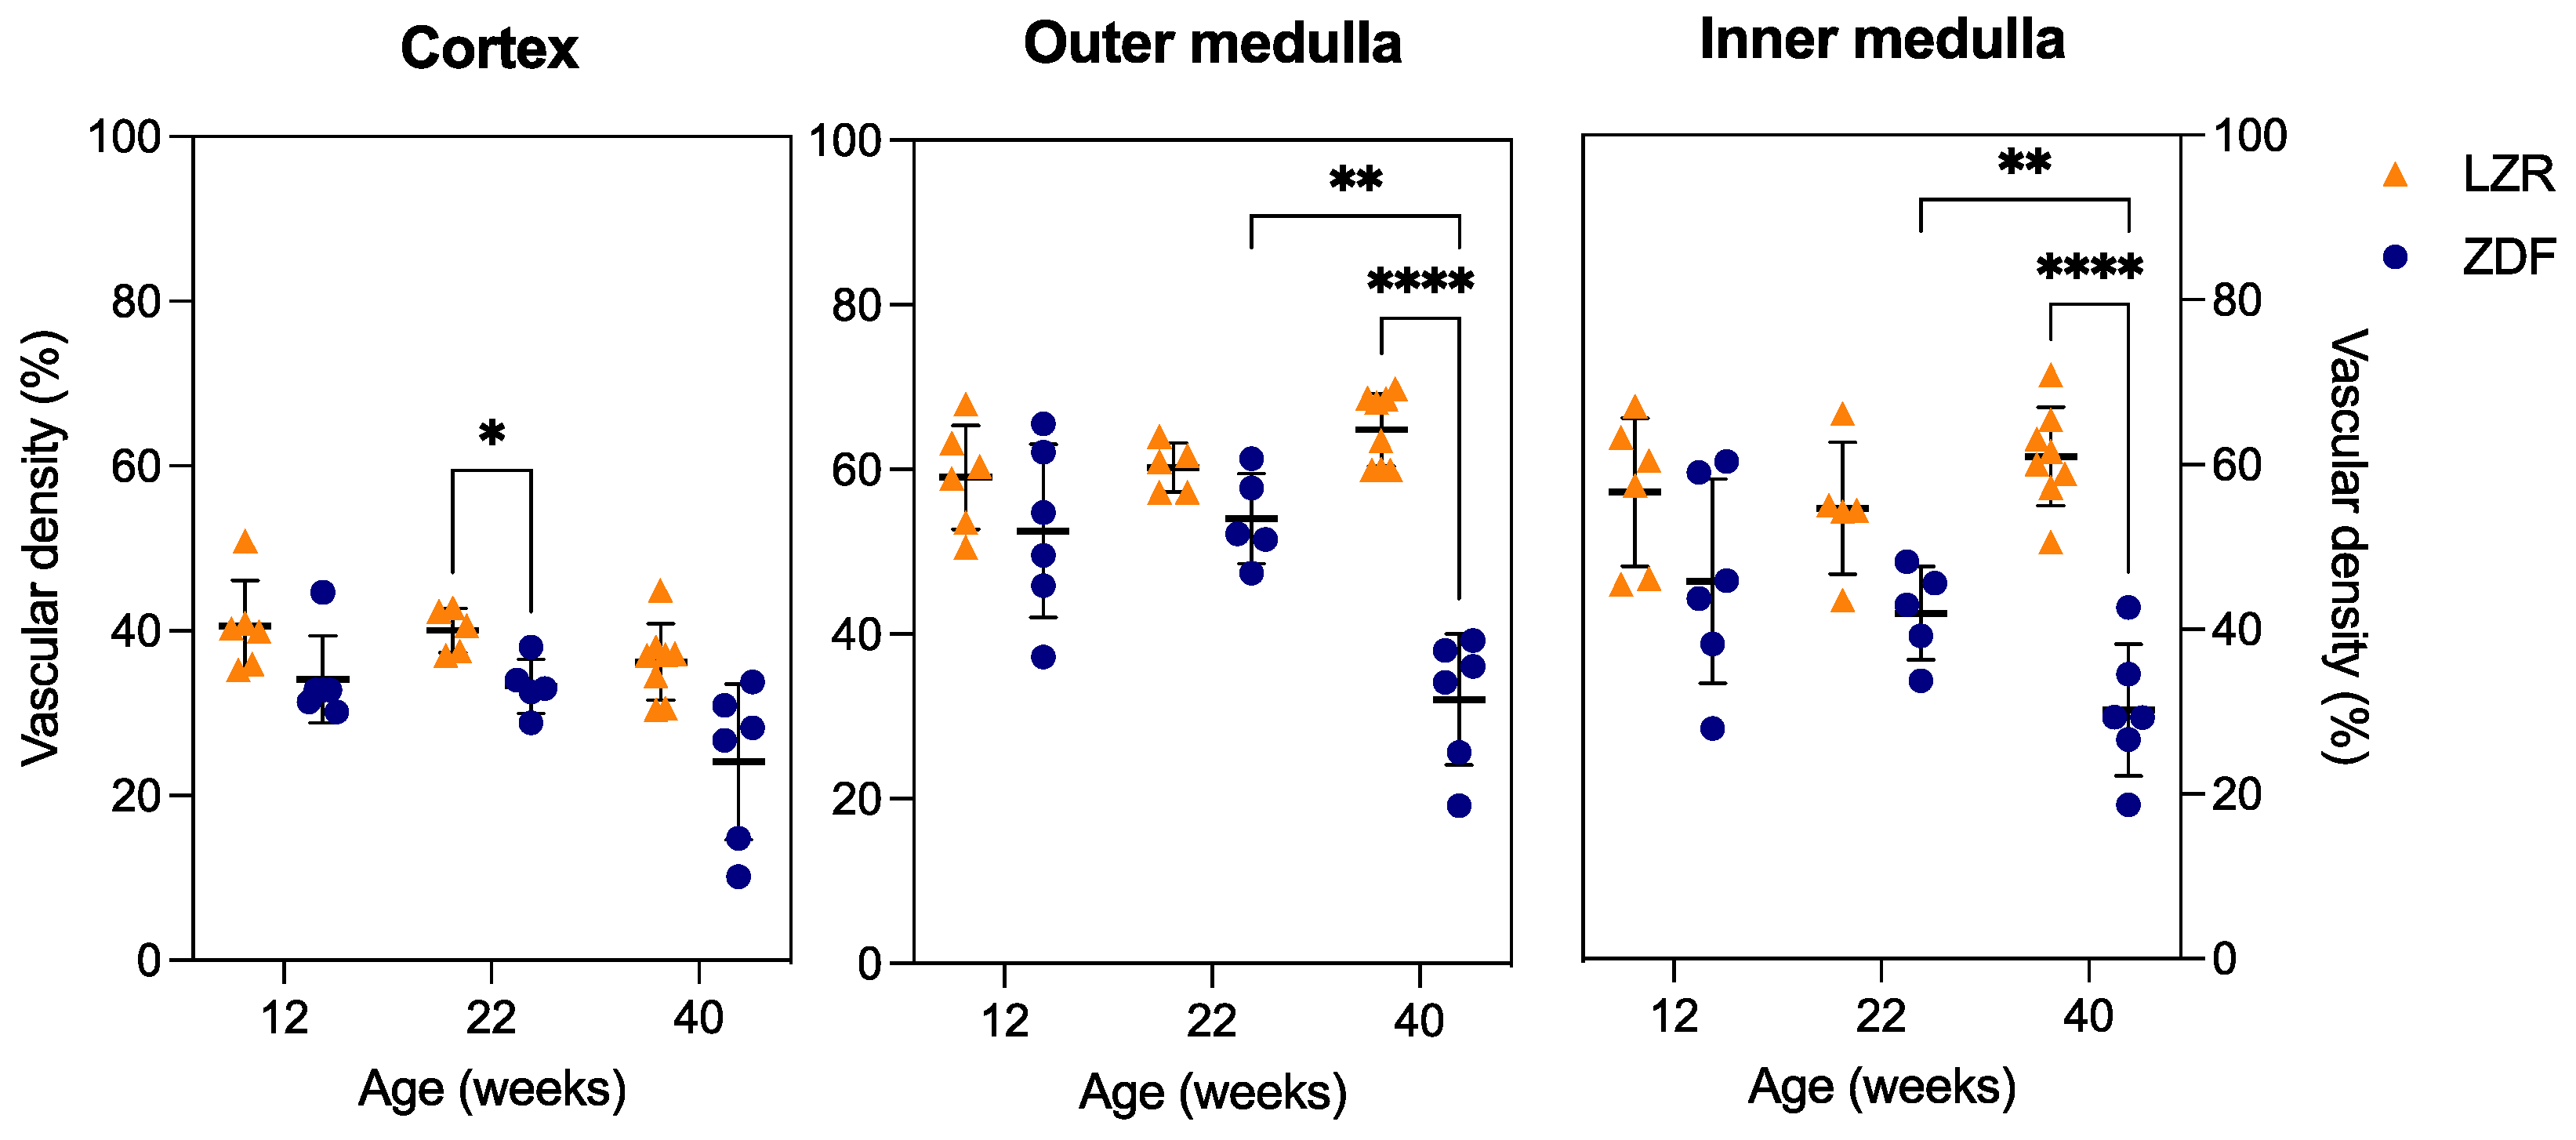

3.4. Qualitative and Quantitative Assessment in µCT